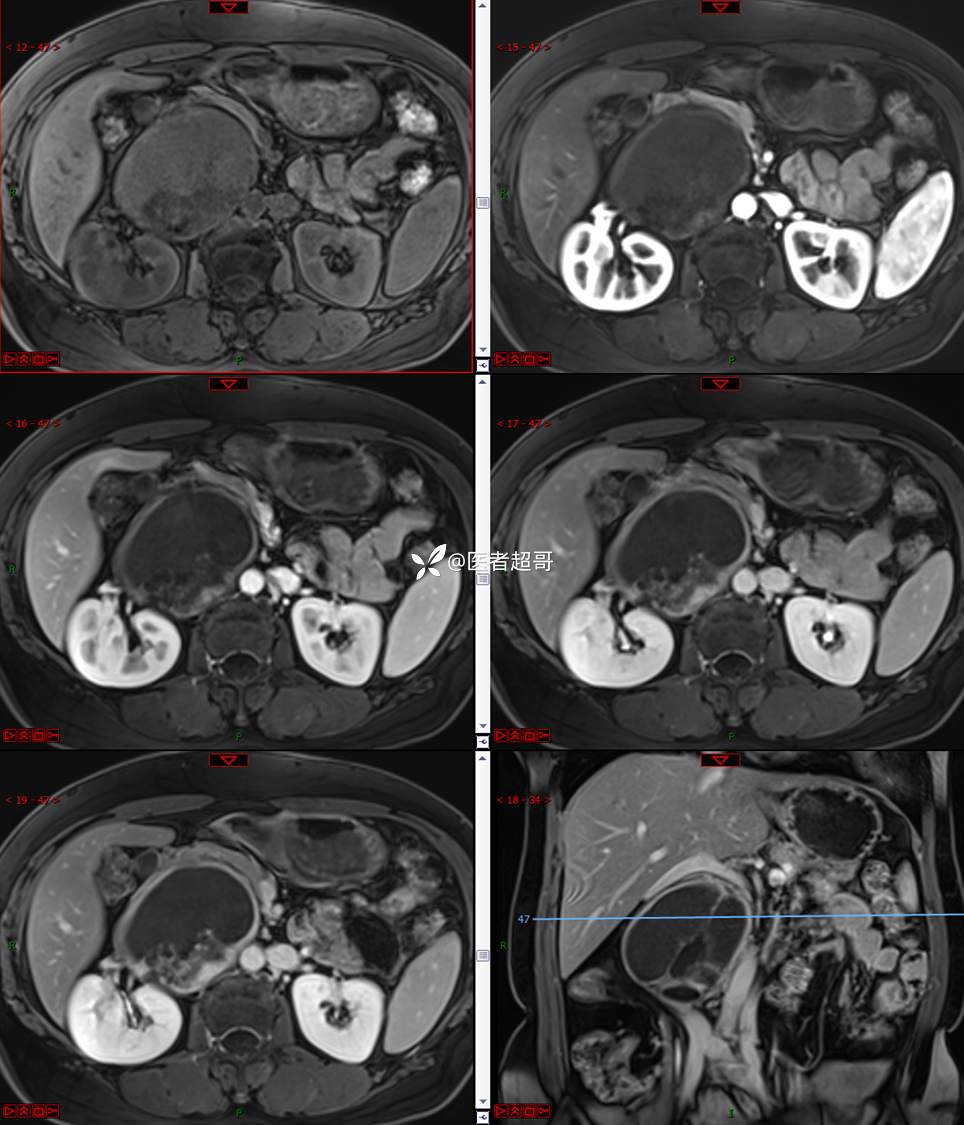

【影诊笔记671】定位有难度,究竟是腹腔内or腹膜后,请先定位,再定性!有结果~~~

专科检查:腹部平坦,腹肌软,无压痛及反跳痛,无包块,肝脾无肿大,Murphy征阴性,腹部叩鼓,肝脾双肾无叩痛,移动性浊音阴性,肠鸣音正常。我院 肝胆胰脾肾彩超提示:脂肪肝、腹腔内囊实性团块,建议进一步检查。